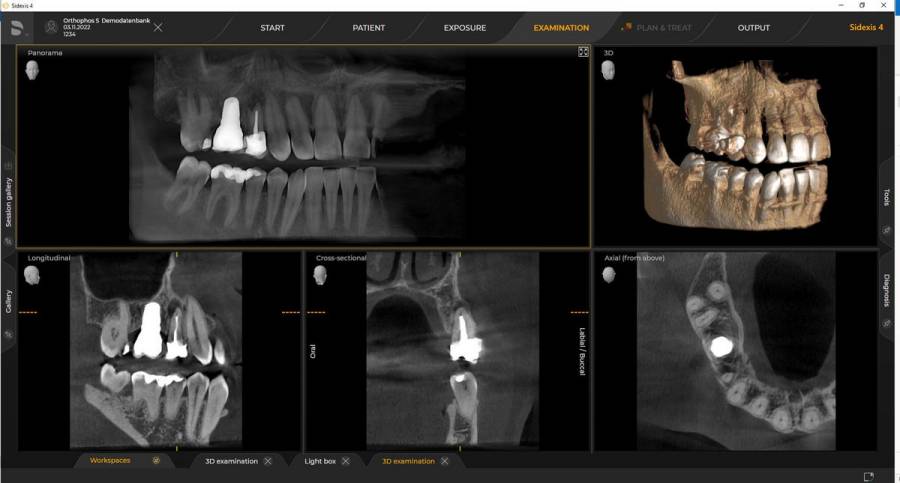

Technologie 3D (tomographie volumique à faisceau conique) pour des images très précises des dents et de l'os. Indispensable pour l'implantologie et la chirurgie.